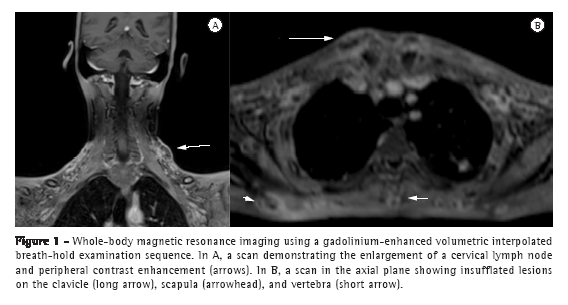

Before the necessary treatment was started, written informed consent was obtained and the patient was submitted to whole-body MRI in order to further investigate the systemic involvement of the disseminated disease. The examination revealed extensive involvement at multiple locations throughout the body, including the subcutaneous tissue, lymph nodes, skeletal system, pleural cavity, and peritoneal cavity. Lymph node enlargement was seen on whole-body MRI in multiple lymph node chains. On a gadolinium-enhanced volumetric interpolated breath-hold examination (VIBE) sequence, the lymph nodes presented peripheral contrast enhancement (Figure 1A). On a short-tau inversion-recovery (STIR) sequence, the central portions of those lymph nodes exhibited hyperintense signals, giving them a necrotic appearance.

On T1-weighted images, the skeletal lesions varied from hypointense to isointense, exhibiting, at some sites, cortical bone destruction and an extensive soft tissue component. In a gadolinium-enhanced VIBE sequence with fat suppression, the lesions exhibited an insufflating pattern, with contrast enhancement predominantly in the peripheral regions (Figures 1B and 2A). On a STIR sequence, the central portions of the lesions presented hyperintense signals, suggestive of necrotic tissue.